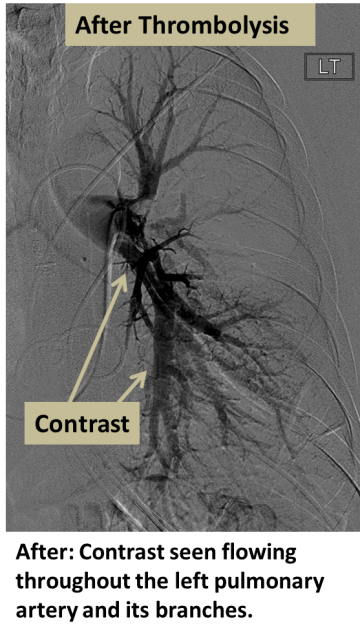

An artery, usually the femoral artery, is accessed with a small puncture, and X-rays are used to navigate a catheter into the occluded artery. A specialized infusion catheter is positioned within or across the clot, and a powerful clot-busting medication (thrombolysis) is dripped into the clot to dissolve it. Follow-up angiography is typically performed in 12-24 hours to determine the success of thrombolysis.